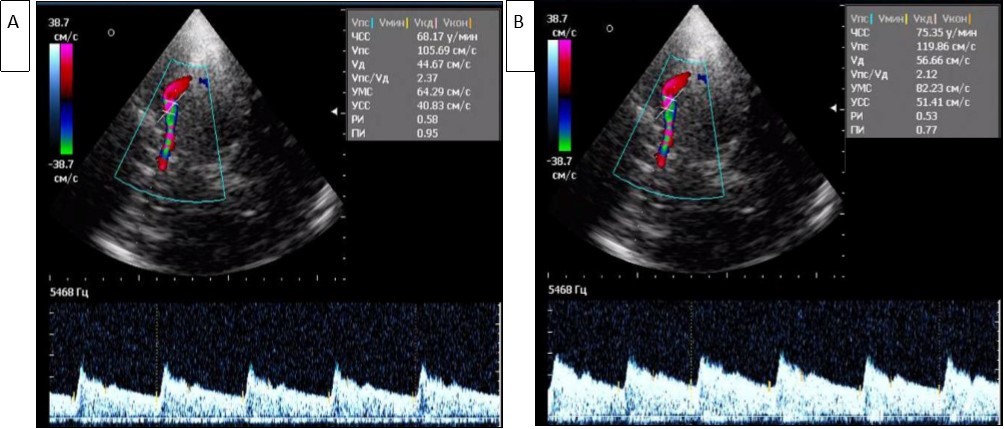

The asymmetry of the maximum systolic blood flow velocity (Vs) in the paired arteries within 20-30% was considered a violation of cerebral hemodynamics, which was detected in 38.7% of patients. An increase in Vs was noted in MCA in patients with Ch TTH and FE TTH compared with the control group (Figure 1, Figure 2A and B).

Figure 2.Registration of blood flow in the left (A) and right (B) middle cerebral arteries in triplex mode (A). High and asymmetric Vs (105 cm/s and 119 cm/s) are determined in the middle cerebral arteries.